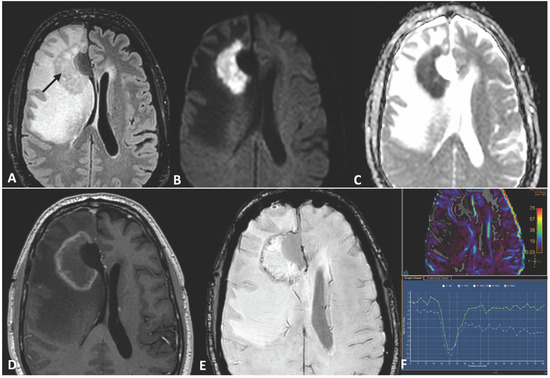

2. Case Report